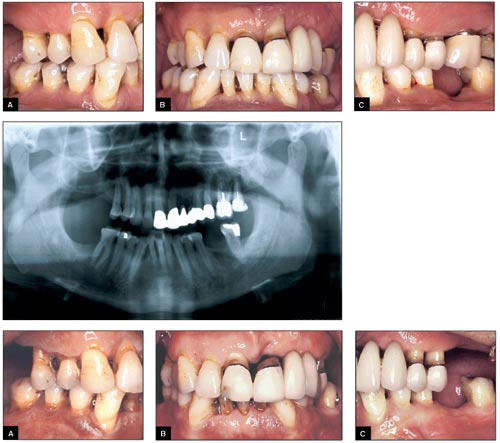

Fig. 2 – 4. Patientfall 1.

Fig. 2 (överst) A-C. Kliniska foton vid första undersökningstillfället.

Fig. 3 (midt). Panoramaröntgen i anslutning till primärundersökningen.

Fig. 4 (nederst) A-C: Kliniska foton efter icke-kirurgisk och kirurgisk behandling.

Den första patienten är en man född 1943 som remitterats till specialistkliniken för parodontologi i Malmö för generell grav parodontit. Patienten uppger sig vara fullt frisk och tar inga mediciner. Han har inga kända allergier och han tål lokalbedövning samt penicillin. Patienten röker inte.

Patienten har normala bettförhållanden men saknar samtliga 8:or och enstaka tänder i sidopartierna. Han har en större bro i överkäken från 11 – 25. Tunga och slemhinnor är utan anmärkning.

Den parodontala undersökningen visar bland annat följande: andelen tandköttsfickor >5 millimeter är 31 procent, PLI = 52 procent och BOP = 37 procent.

Parodontal diagnos: Generell kronisk parodontit med gravis et complicatakaraktär.

Behandlingen består inledningsvis av extraktioner av tänder med dålig prognos det vill säga 21, 26 och 27. Samtidigt genomförs en intensiv hygienbehandling som består av information om sjukdomen, upprepade instruktioner i munhygien samt supra- och subgingival depuration. Därefter genomförs parodontalkirurgi, både gingivektomi och modifierad Widman-lambå vid kvarstående fördjupade tandköttsfickor som uppvisar patologi.

Drygt ett år efter den kirurgiska behandlingen har andelen fördjupade tandköttsfickor >5 millimeter reducerats till 4 procent, PLI=11 procent och BOP=3 procent.

Hela bettet har en god prognos under förutsättning att patienten fortsätter med sina munhygienrutiner och kommer på regelbundna stödbehandlingsbesök.